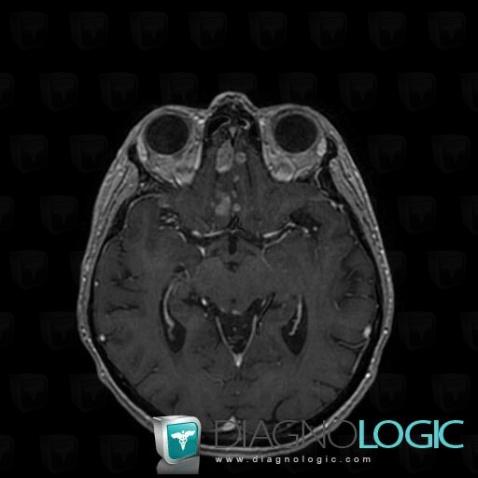

Voici les informations spécifiques à l'image clé ci dessus:

- Diagnostic Méningite carcinomateuse, Localisation(s) Région cortico sous corticale, comportant les gammes Lésion corticale

Voici les informations spécifiques à l'image clé ci dessus:

- Diagnostic Méningite carcinomateuse, Localisation(s) Espaces peri cérébraux infratentoriels, comportant les gammes Lésion extra axiale infra tentorielle